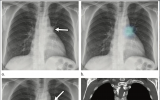

X射線檢查顯示COVID-19如何使身體自行攻擊

雖然肌肉酸痛和關節疼痛是COVID-19患者的常見癥狀,但有些人會經歷更嚴重和更長時間的病征,例如類風濕性關節炎發作,自身免疫性肌炎或“COVID腳趾”,即一種皮膚病,患者的腳趾會腫脹變色,帶有水泡或膿皰。西北醫學大學的研究人員說,放射影像首次證實了這些癥狀的起因是身體本身。 2021-02-20